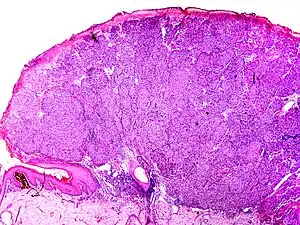

The microscopic hallmarks are:

- Dome-shaped at low power

- Epidermis thin or normal

- Dermal nodule of melanocytes with a 'pushing' growth pattern

- No "radial growth phase"